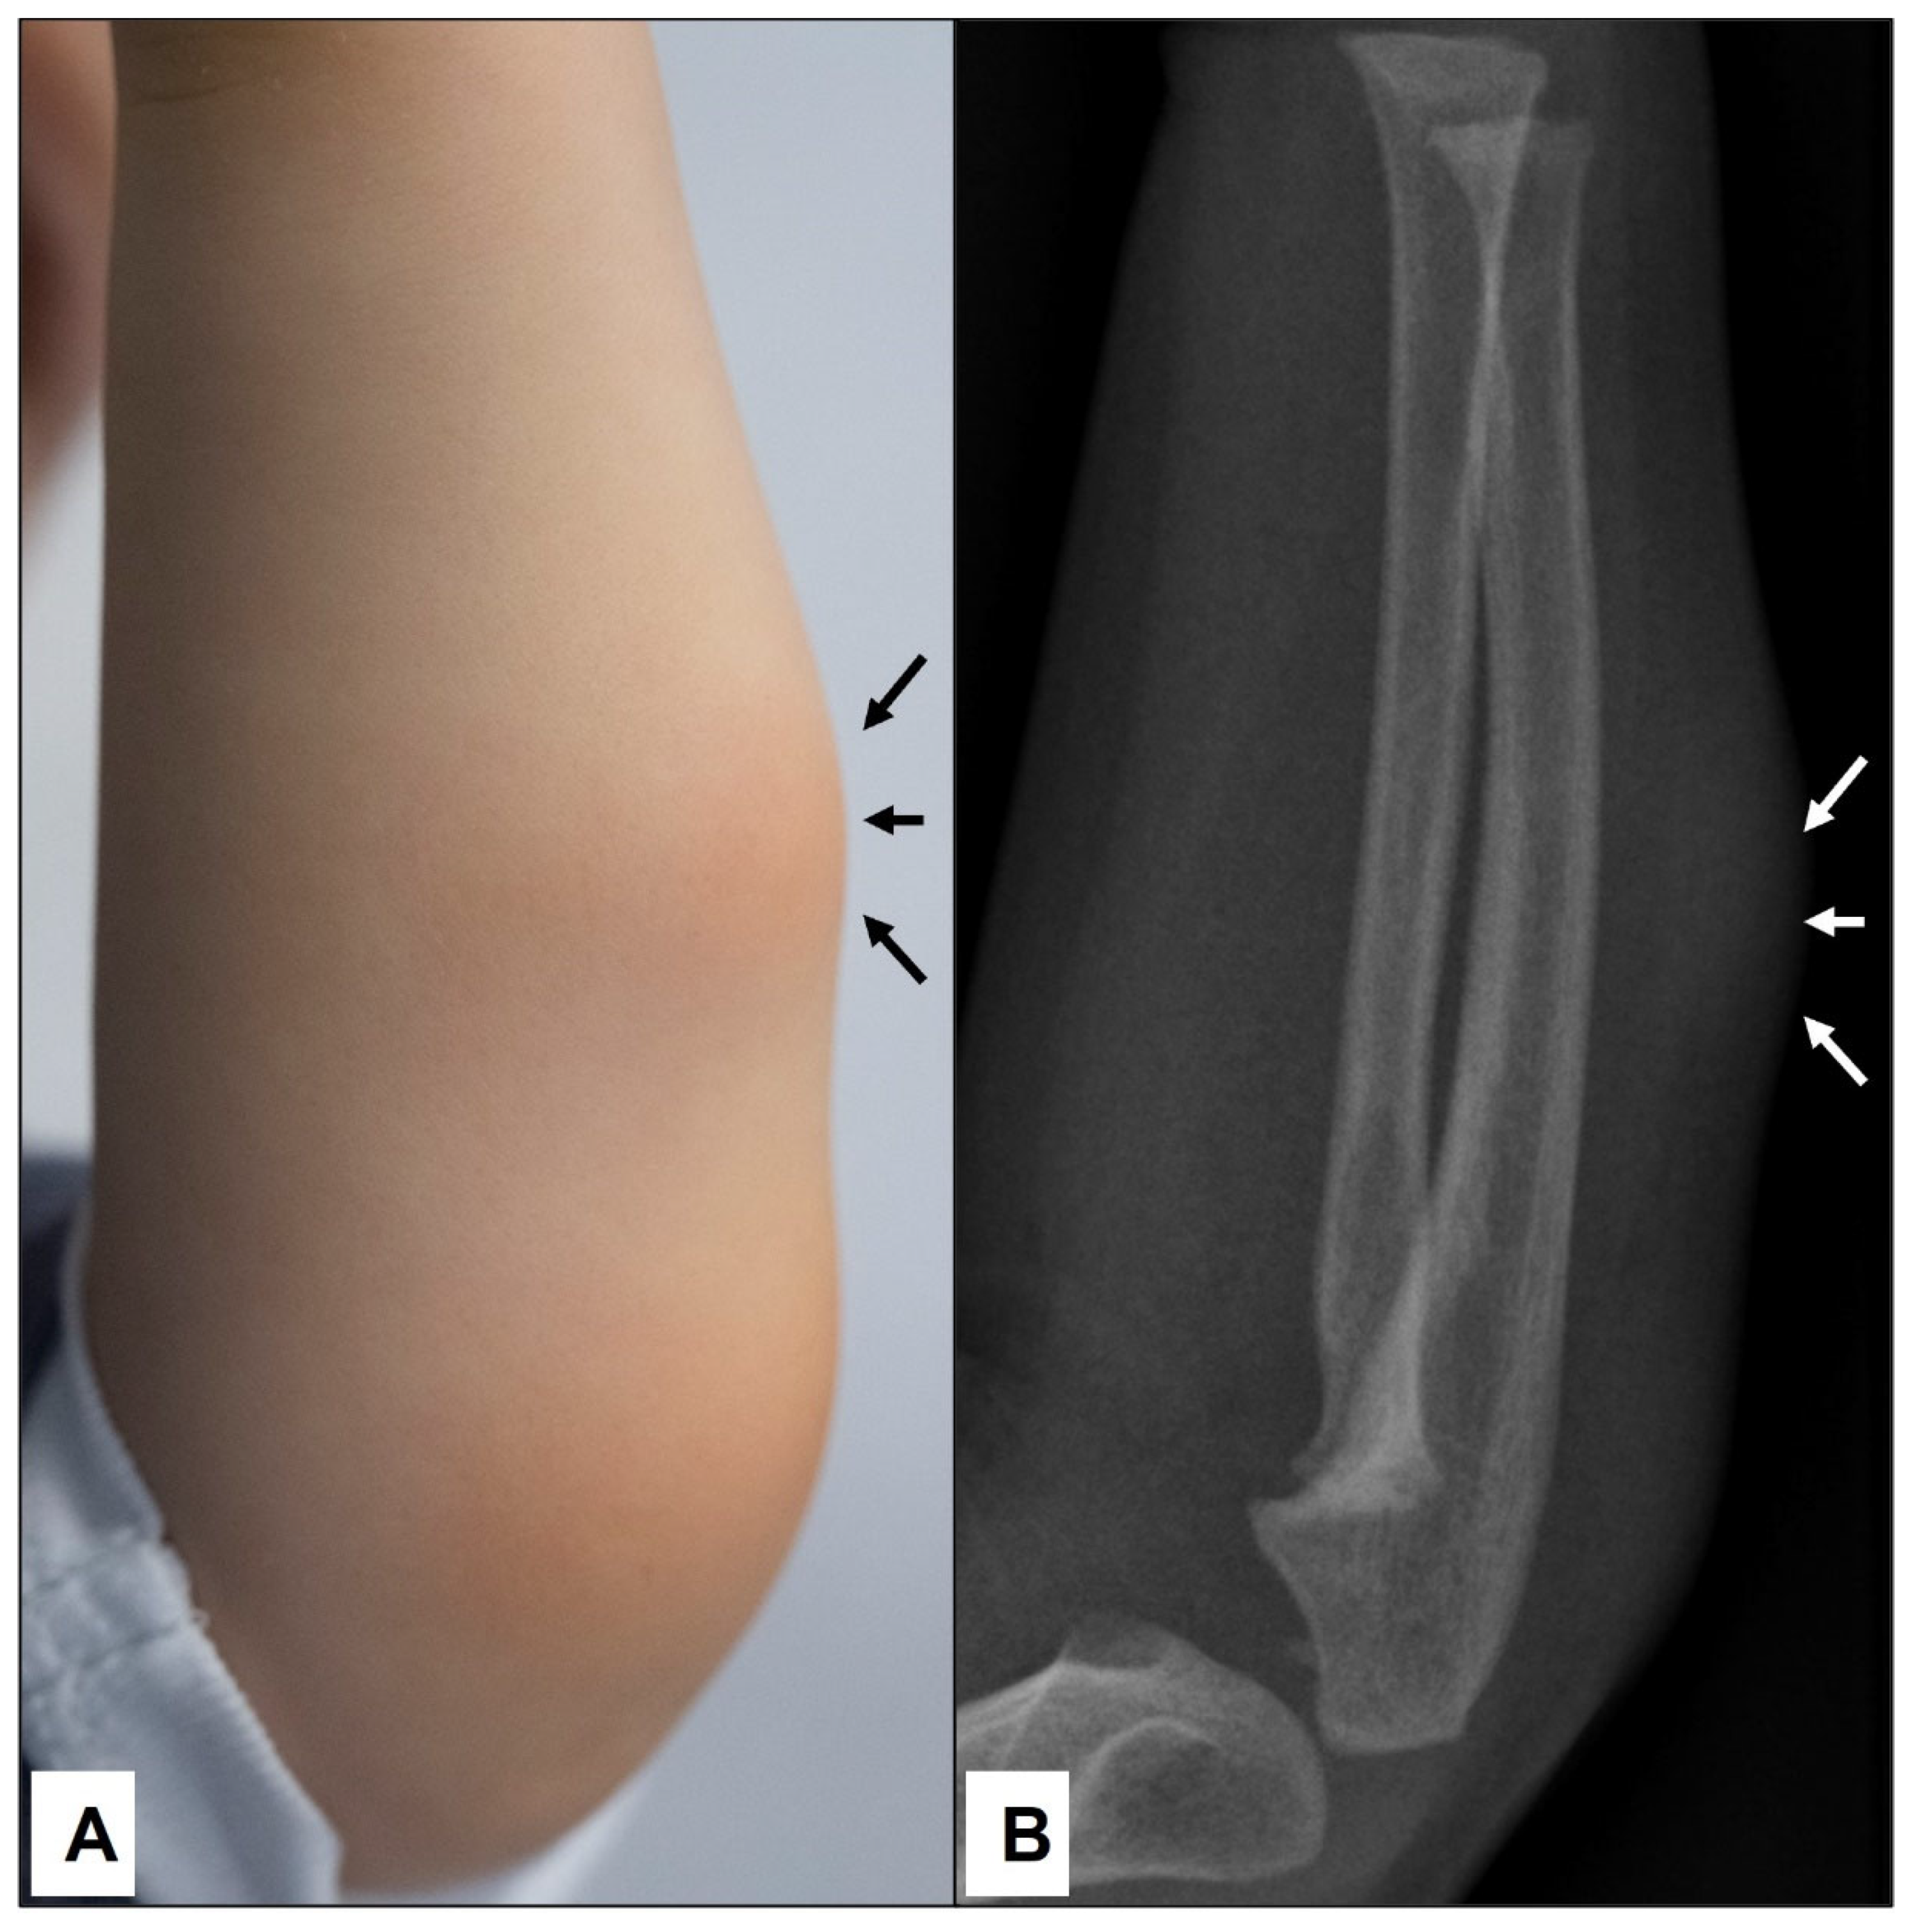

Figure 3.

A 2-year-old boy was presented by his parents due to the swelling on the left forearm, which persisted for the last 2 months (A)—(black arrows). Because the subcutaneous lump was firm and immobile, an X-ray was conducted to exclude bone abnormalities (B). Note the homogenous soft tissue expansion in the subcutaneous area (white arrows) but no osseous involvement.